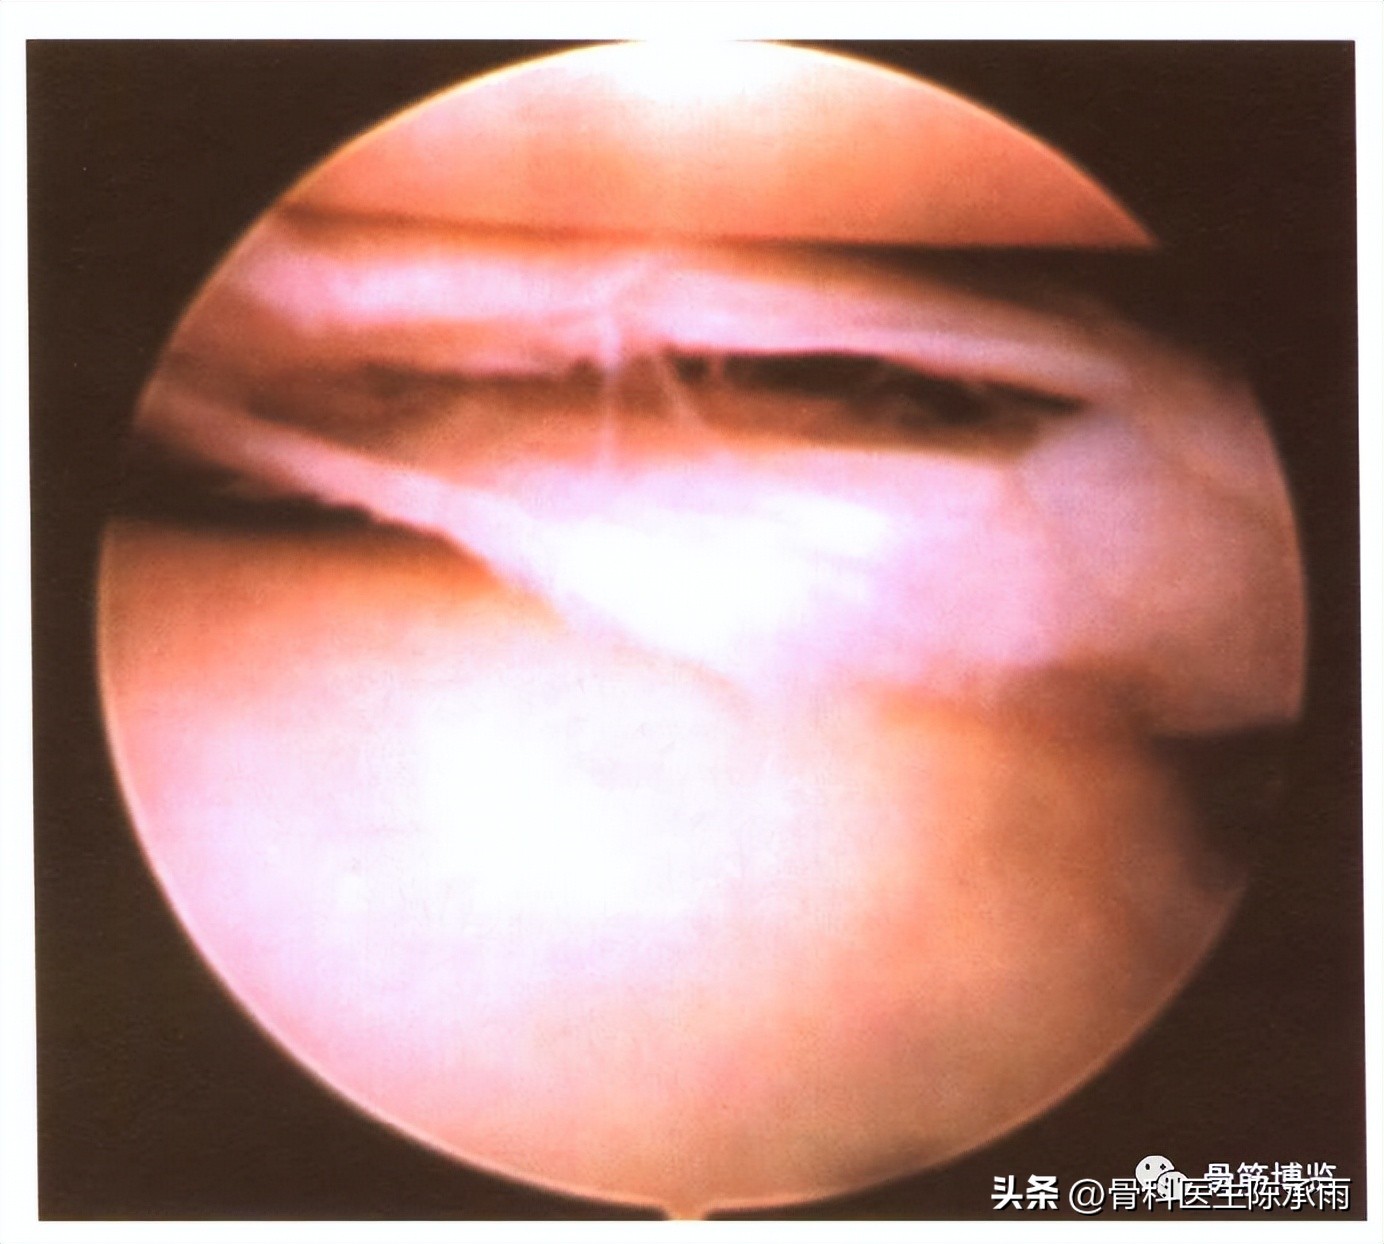

(四)活瓣状裂

另外有一部分非全层的斜裂形成舌状,或在股骨面上,或在胫骨面上,或向前反折或向后反折形成活瓣状撕裂。